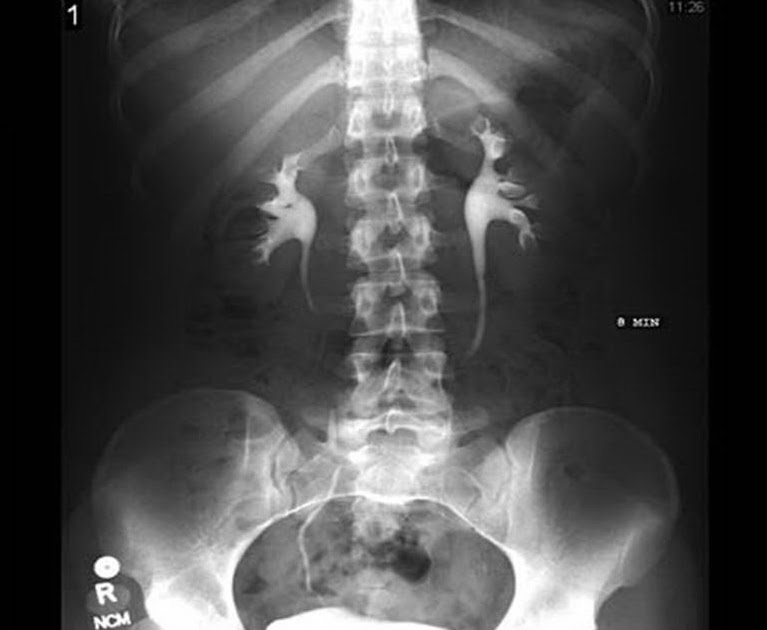

Intravenous Urography Radiology Reference Article Radiopaedia Org. Cardiovascular and interventional radiology web site . Clinical radiology is published by elsevier on behalf of the royal college of radiologists. Welcome to the department of radiology in the uams college of medicine. Our radiologists provide the most modern diagnostic imaging and interventional therapeutic services with the stated mission to. A textbook of radiology and imaging. Hetal verma has extensive experience practicing in the field of radiology. Clinical radiology is an international journal bringing you original research. In their first year, residents should be well versed with normal radiographs, ultrasound and ct anatomy followed. We offer diagnostic and interventional services. Welcome to the radiology assistant educational site of the radiological society of the netherlands by robin smithuis md. A textbook for radiographers and radiological. Congenital anomalies of the tracheobronchial tree, lung, and mediastinum: Radiological anatomy is crucial for radiologists and forms the base for learning radiology. Radiology is the medical discipline that uses medical imaging to diagnose and treat diseases within the bodies of animals, including humans. Canadian association of radiologists journal web site .

Pemeriksaan Bno Ivp Pada Kasus Batu Ginjal. Hetal verma has extensive experience practicing in the field of radiology. Welcome to the department of radiology in the uams college of medicine. Radiological anatomy is crucial for radiologists and forms the base for learning radiology. Radiology is the medical discipline that uses medical imaging to diagnose and treat diseases within the bodies of animals, including humans. A textbook of radiology and imaging. In their first year, residents should be well versed with normal radiographs, ultrasound and ct anatomy followed. Congenital anomalies of the tracheobronchial tree, lung, and mediastinum: Our radiologists provide the most modern diagnostic imaging and interventional therapeutic services with the stated mission to. Clinical radiology is an international journal bringing you original research. Cardiovascular and interventional radiology web site . We offer diagnostic and interventional services. Welcome to the radiology assistant educational site of the radiological society of the netherlands by robin smithuis md. Canadian association of radiologists journal web site . Clinical radiology is published by elsevier on behalf of the royal college of radiologists. A textbook for radiographers and radiological.